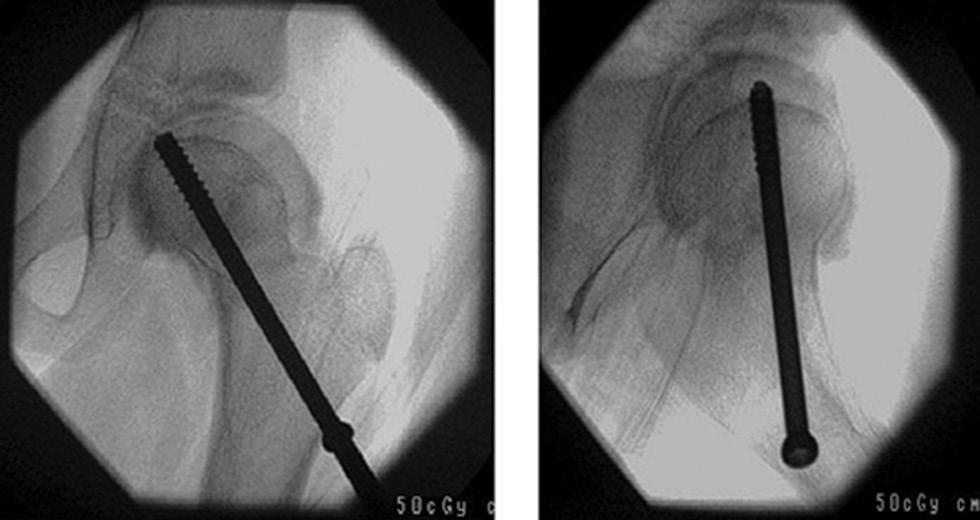

Furthermore, Campbell and Tarlow studied 146 children with dysplasia after conservative treatment and detected dysfunction and closure of the lateral part of the growth zone of the femoral head epiphysis in 14 patients and concluded that this lesion was an iatrogenic pathology caused by traumatization of the head during dislocation repair or after a period of immobilization in the limb abduction position. Premature closure of the lateral edge of the growth plate resulted in a valgus deformity of the femoral neck, shortening, and displacement of the head epiphysis to the greater trochanter. The authors also observed lower extremity length inequalities of 1–5 cm caused by femoral neck shortening and excessive valgus deviation. The authors performed varus intervertebral osteotomy to correct the femoral deformity; however, some patients required revision surgery. As an experiment, a screw was placed in several patients in conjunction with an intervertebral osteotomy to cross the medial growth plate of the physis (Fig. 1), and excellent results were noted [11].

Fig. 1. Medial epiphysiodesis [24]